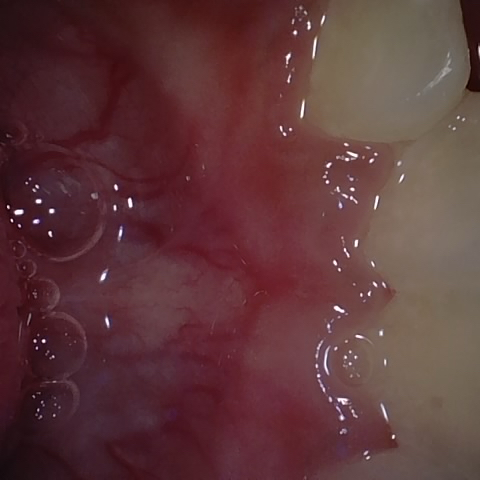

Image 165 / 400

NHD25463

Annotated as "Good"

Original Image Rendering Image